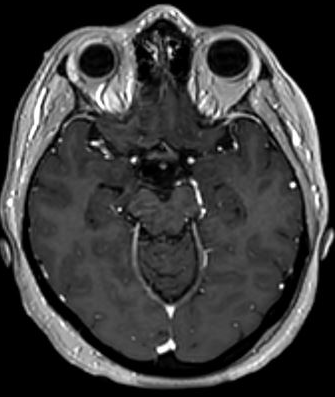

The selection of imaging modality significantly impacts the visualization of cerebrovascular structures, which is crucial for pre-operative neurosurgical planning. TOF-MRA relies on flow-related enhancement to effectively highlight large, fast-flowing arteries. However, as shown in Fig. 1 (a), TOF-MRA is limited in soft tissue contrast and often fails to adequately visualize small, slow-flowing vessels and venous structures. While its focused arterial visualization simplifies segmentation, it frequently results in incomplete vascular maps, particularly around tumor margins or in anatomically complex regions.

In contrast, T1CE MRI uses a gadolinium-based contrast agent to enhance areas of increased perfusion or disrupted blood-brain barriers, typically associated with neoplastic tissue. As depicted in Fig. 1(b), T1CE MRI provides superior soft-tissue contrast and enables visualization of both arteries and veins, including smaller vessels that are often missed by TOF-MRA. This detailed anatomical information is critical for surgical planning, particularly in understanding the tumor-vasculature interface.

Figure 1: Comparison of vascular and tissue visualization in TOF-MRA and T1CE MRI. (a) TOF-MRA highlights large, fast-flowing arteries with limited soft tissue contrast and poor visibility of small or slow-flow vessels. (b) T1CE MRI provides enhanced anatomical detail and visualizes both arteries and veins, including smaller vessels near pathological tissue, but introduces complexity in vessel segmentation due to nonspecific enhancement.